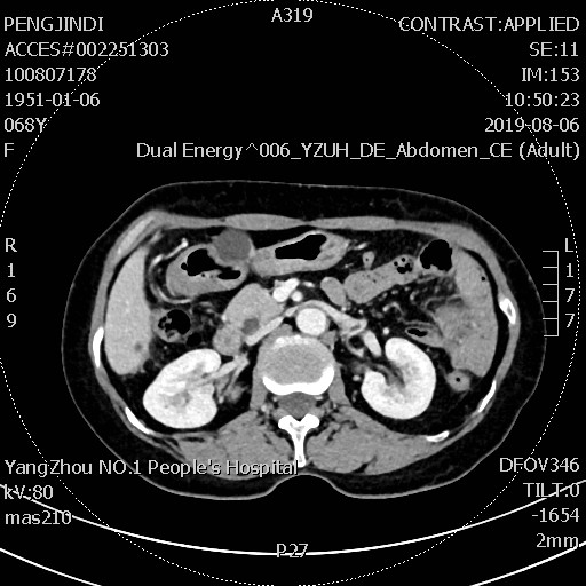

患者无明显腹痛,肠梗阻等症状。2019-08 CT检查:腹盆腔见多发不规则片絮状及结节状稍高密度影,境界欠清。右侧髂窝见少许水样密度影。与前片(20190424)相比:左腹部部分小肠扩张积液好转;盆腔积液大部分吸收。

2019-08-06 CT检查